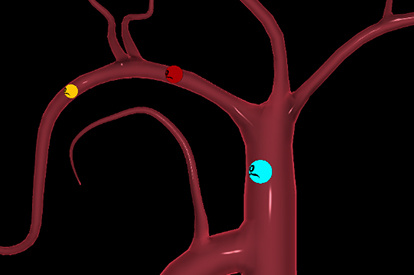

The ANGIO Mentor simulator is an essential tool for clinicians to practice and acquire the skills needed for performing endovascular interventions. Trusted by medical associations, hospitals, training centers, and the medical device industry globally, it provides trainees with realistic clinical settings to practice endovascular interventions using fluoroscopic and ultrasound guidance.

Offers true-to-life simulation of the clinical environment, including advanced imaging modalities like fluoroscopy/echocardiography, hemodynamic monitoring, medications, and interventional devices

Simulates rare and common intra-procedure complications, allowing for realistic training in a safe environment

Peripheral Embolization Module

Embolotherapy (HCC & UFE) Module

Advanced Embolization Module